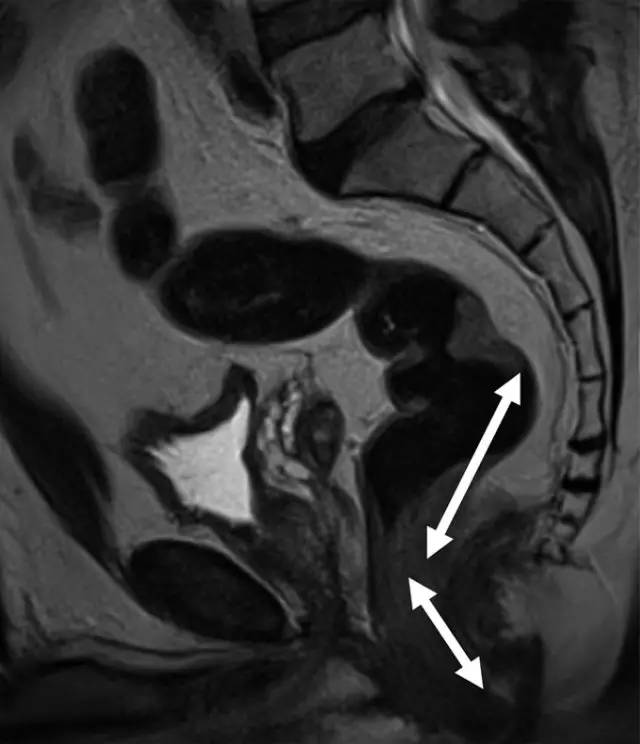

图 2 中位直肠癌患者的矢状 T2 加权图像。箭头显示肿瘤下缘距离肛缘 5~10 cm。